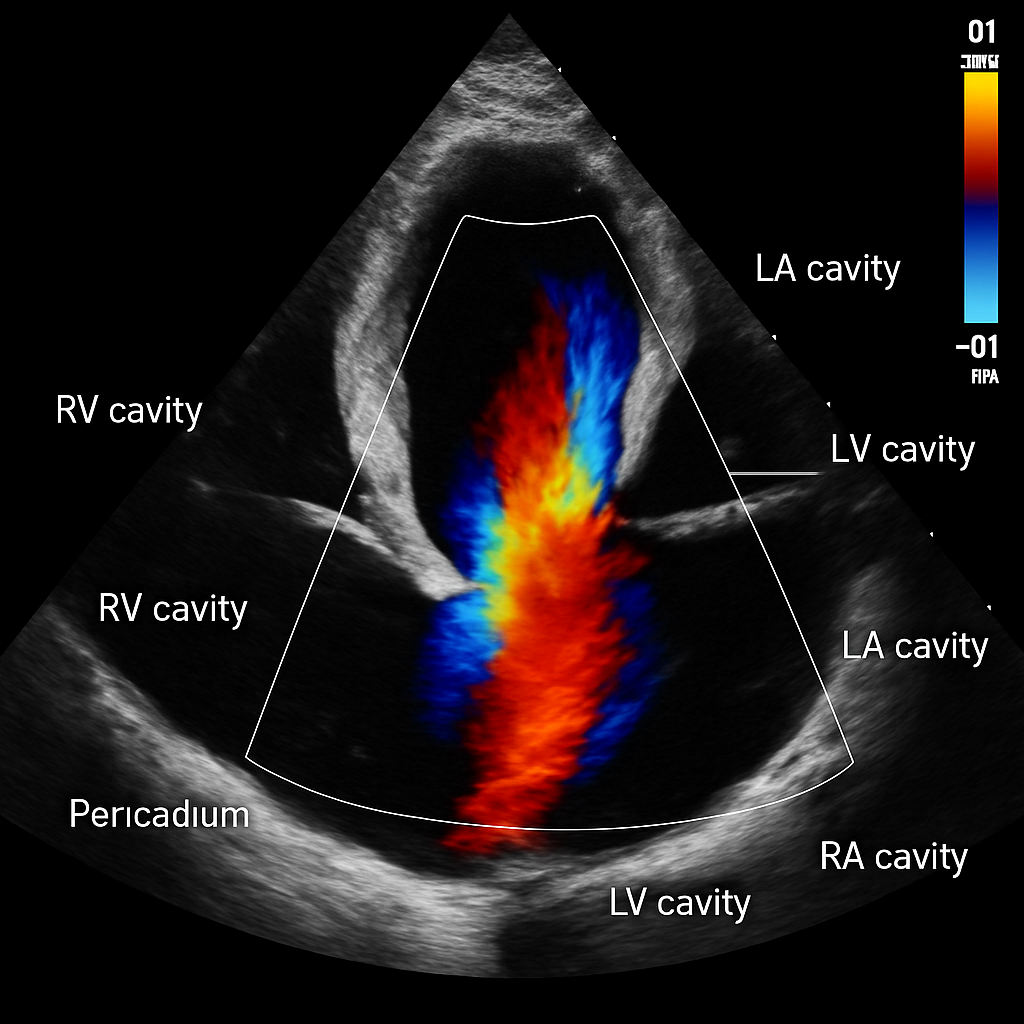

Echo — Color Doppler Mitral Valve

Color Doppler echocardiogram showing blood flow through the mitral valve in apical four-chamber view. Red-blue color map showing laminar diastolic inflow.

ULTRASOUND AI Generated 2026-03-16

Color Doppler Mitral

Color Doppler overlay on A4C view. Red = flow toward transducer (mitral inflow). Show color velocity scale bar.

OpenAI gpt-image-1